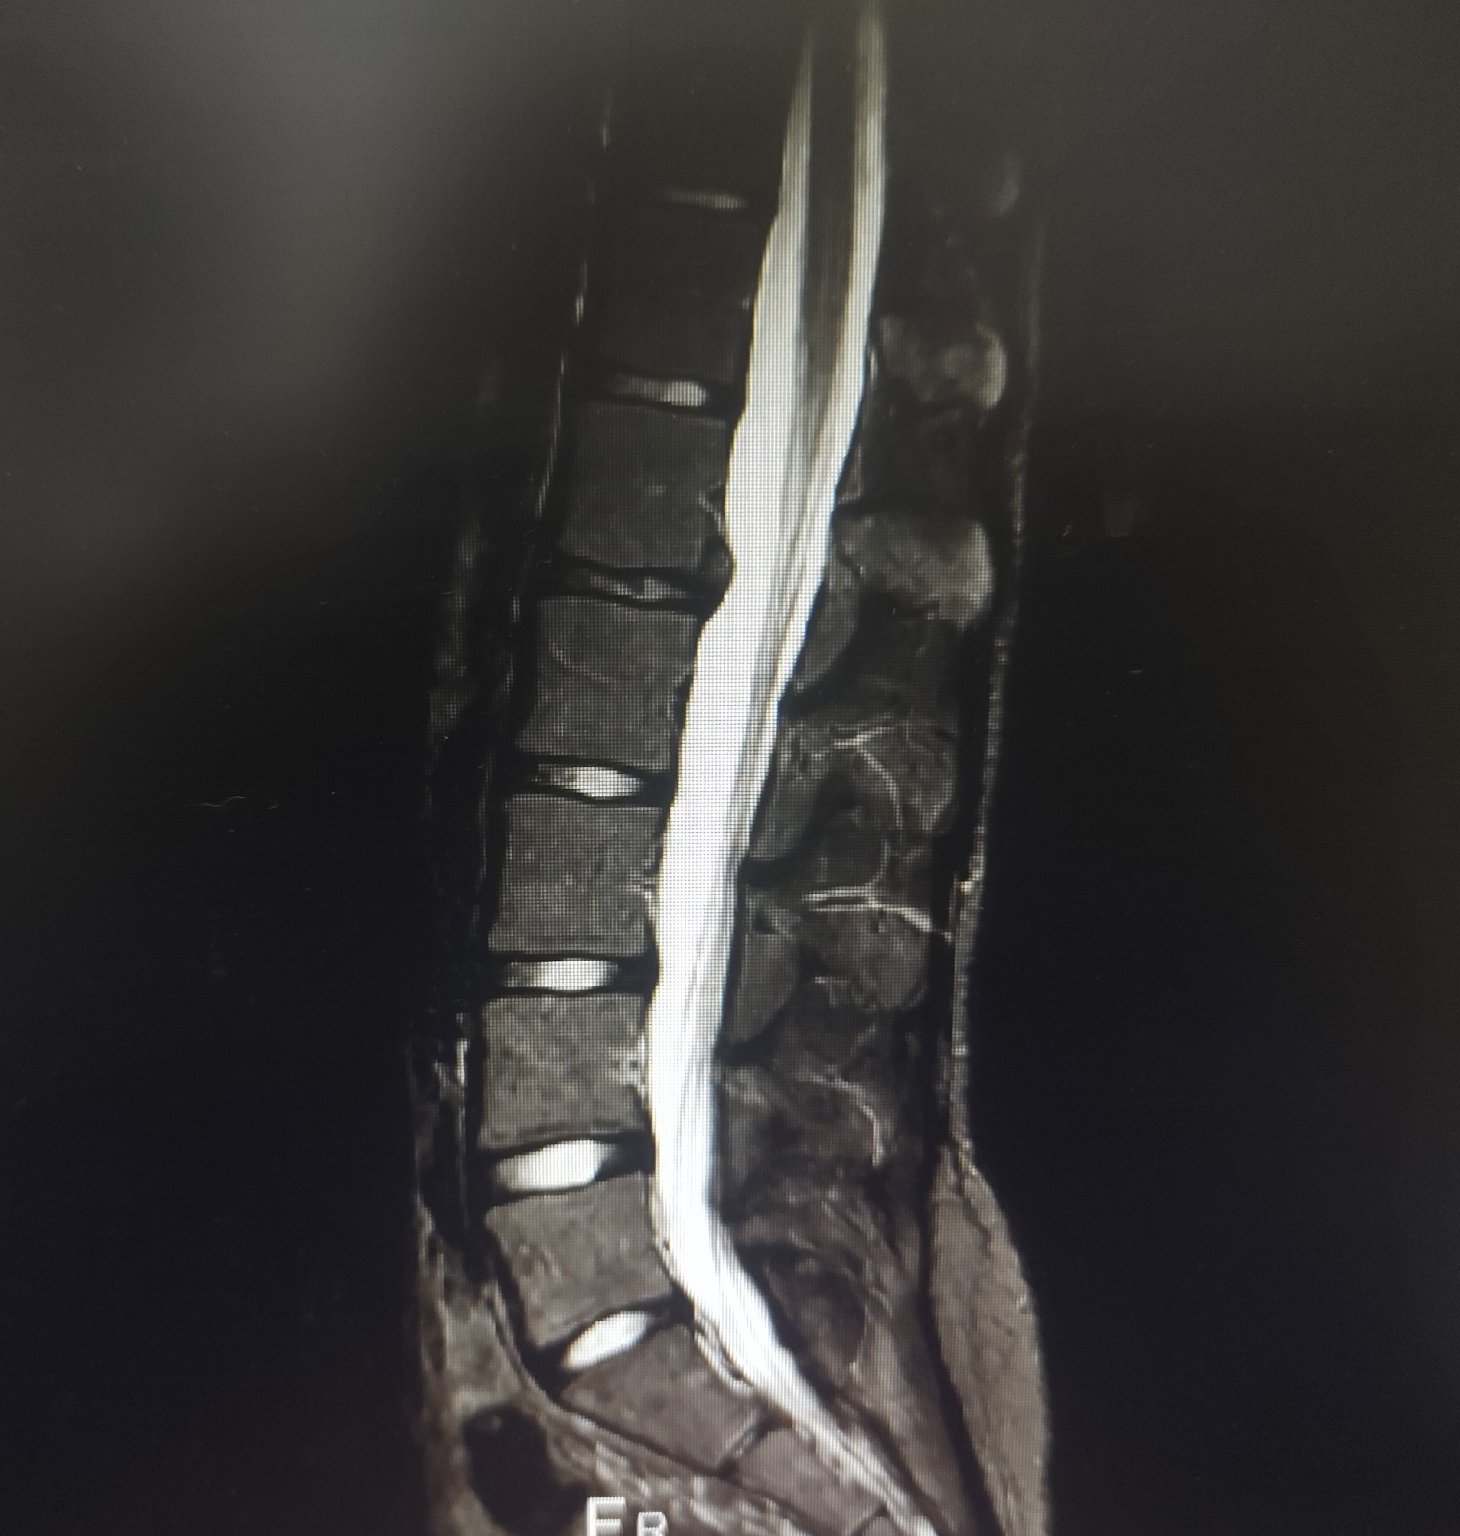

Милички , помагайте, това е нов mri , какво мислите?

Човека е почти неподвижен, мъж на 53.

Как така почти неподвижен? Според този разчет, не би трябвало да е почти неподвижен, ами да има радикулопатия по десен крак. Може би проблемът да идва от ставите, по-скоро?